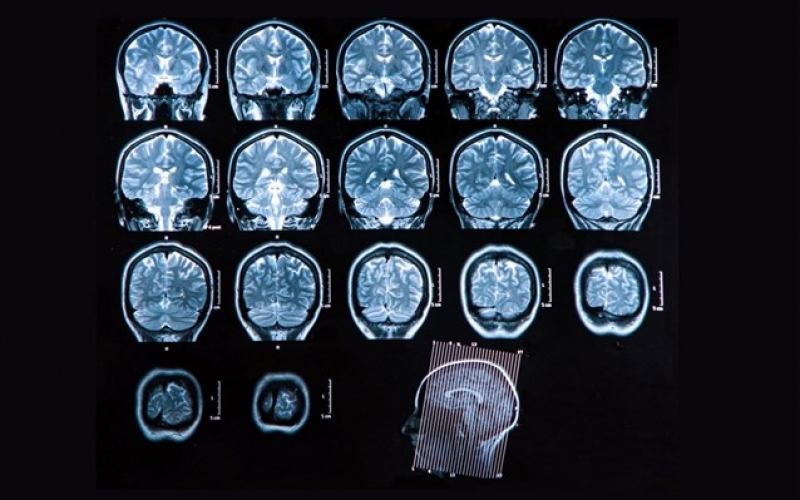

συγκεκριμένα για τη συγκεκριμένη ασθένεια (μη συγκεκριμένα), αλλά μπορούν να συσχετιστούν με πολλές άλλες καταστάσεις. Τα σύγχρονα διαγνωστικά μέσα απεικόνισης έχουν επιτρέψει την αναγνώριση μορφών σκλήρυνσης κατά πλάκας στα οποία οι αλλοιώσεις που είναι χαρακτηριστικές της νόσου είναι παρούσες στον εγκέφαλο, χωρίς να εκδηλώνονται ποτέ συμπτώματα. αυτή η κατάσταση ονομάζεται ραδιολογικώς απομονωμένο σύνδρομο (στο αγγλικό ραδιολογικώς απομονωμένο σύνδρομο: RIS).